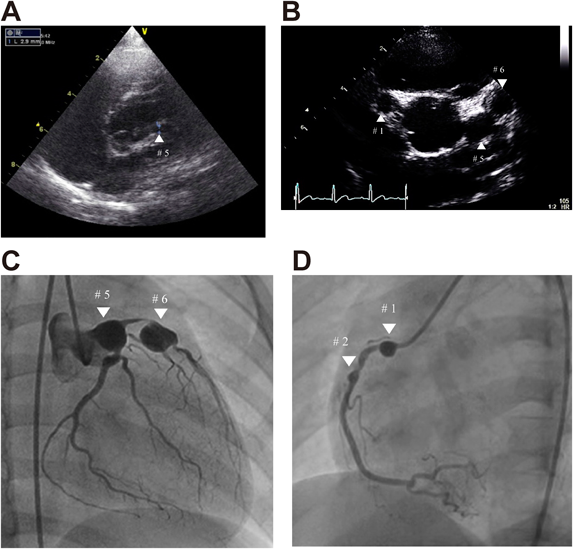

Fig. 1 Echocardiographic and angiographic findings in Case 1

(A) Echocardiogram performed in Case 1 during the acute phase of Kawasaki disease at a local hospital. Retrospectively, only the proximal part of the left coronary artery could be visualized (white ▲). (B) Echocardiogram in Case 1 performed at school cardiac screening. The parasternal short axis of the aortic root demonstrated the presence of bilateral coronary artery aneurysms (white ▲). The diameter of the right coronary artery aneurysm was 7.4 mm at #1 and those of left coronary artery aneurysms were 9.1 at #5 and 9.5 mm at #6, respectively. (C) Left coronary angiography in Case 1 demonstrating coronary artery aneurysms of 10.7 mm and 12.3 mm in diameter at segment 5 and segment 6 (white ▼), with a 99% stenosis between the aneurysms. (D) Right coronary angiography in Case 1 demonstrating coronary artery aneurysms of 6.6 mm and 3.1 mm in diameter at segment 1 and segment 2 (white ▼).

Cardiac catheterization and coronary angiography (Fig. 1C and D) confirmed CAAs with maximum diameters of 10.8 mm, 12.3 mm, and 6.6 mm at segments 5, 6, and 1, respectively, and 99% stenosis between the CAAs of segments 5 and 6. After plain old balloon angioplasty was performed at the stenotic lesion and stenosis was successfully improved, follow-up coronary angiography after 8 months of angioplasty showed asymptomatic complete occlusion of giant CAA at segment 6. Because stress technetium myocardial perfusion scintigraphy using adenosine induced chest pain and obvious ST segment depression in V2–4, the patient was scheduled to undergo coronary artery bypass grafting and underwent a special treatment program with regular heparin infusion and exercise.4) Regular echocardiography showed suspected stenosis on the proximal side of the CAA at segment 1. The patient was transferred to another hospital where he underwent successful coronary artery bypass grafting (left internal mammary artery to the left anterior descending artery). Since then, he recovered without further intervention.